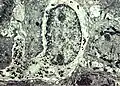

Melanocytes in basal cells of a smoker's gum -

The microscope shows a smoker's melanosis to be characterized by a melanin hyperpigmentation of the lower part of the oral epithelium, similar to sun-tanned skin. The hyperpigmentation consists of melanin granules which have the shape and colour of "coffea beans". They are produced by the dendritic, octopus-like melanocytes, seen between the epithelial cells situated closest to the epithelium/connective tissue border.[7]

In tobacco-users the melanocytes are stimulated to produce melanin granules and to distribute them out to the surrounding epithelial cells for further transport to the mucosal surface, like the mechanism in melanin-pigmented skin.